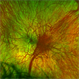

- foveal hypoplasia

- Composite.